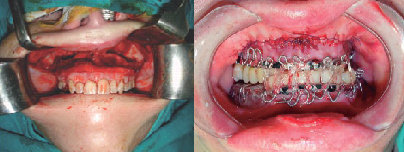

FRACTURAS DE MANDÍBULA

FRACTURAS PANFACIALES